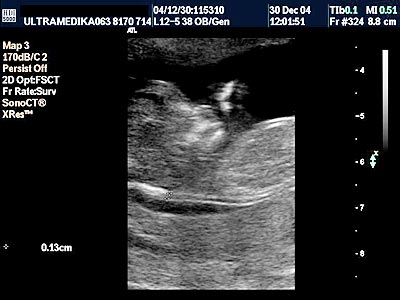

1. Da li je trudnoća materična

ili vanmaterična?

Na razne načine se može utvrditi postojanje trudnoće . Međutim ova konstatacija nije dovoljna. Povremeno se može desiti da je trudnoća vanmaterična (EU)! Na standardnom UZ pregledu se ne registruje gestacioni sac - GS (vreća u kojoj počinje da se razvija plod) unutar šupljine materice. Od kvaliteta ultrazvučnog aparata i iskustva i znanja doktora zavisi blagovremeno otkrivanja ovog bolesnog stanja žene. Naime blagovremeno otkriti GS u abdomenu, ili u jajovodu predstavlja veliki problem. Osim toga GS može biti pogrešno smešten u grliću materice ili na mestu prethodnog Carskog reza. KOMPJUTERIZOVANA ULTRAZVUČNA DIJAGNOSTIKA-Sono CT i Xres, koristi više ultrazvučnih talasa iz raznih pravaca za razliku od konvencionalne tehnika i omogućava znatno precizniju 2D sliku. Posebna tehnika-HARMONIK MOD za uklanjanje artefakata nastalih od crevnih vijuga je takođe nezamenjiva u otkrivanju rane vanmaterične trudnoće. Blagovremena dijagnoza vanmaterične trudnoće omogućava medikamentno lečenje bez hirurške intervencije.